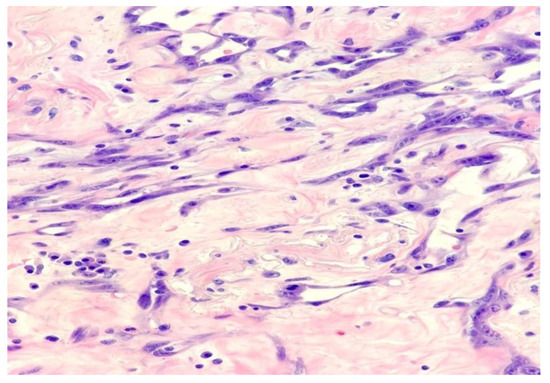

2. Case Report and Evolution